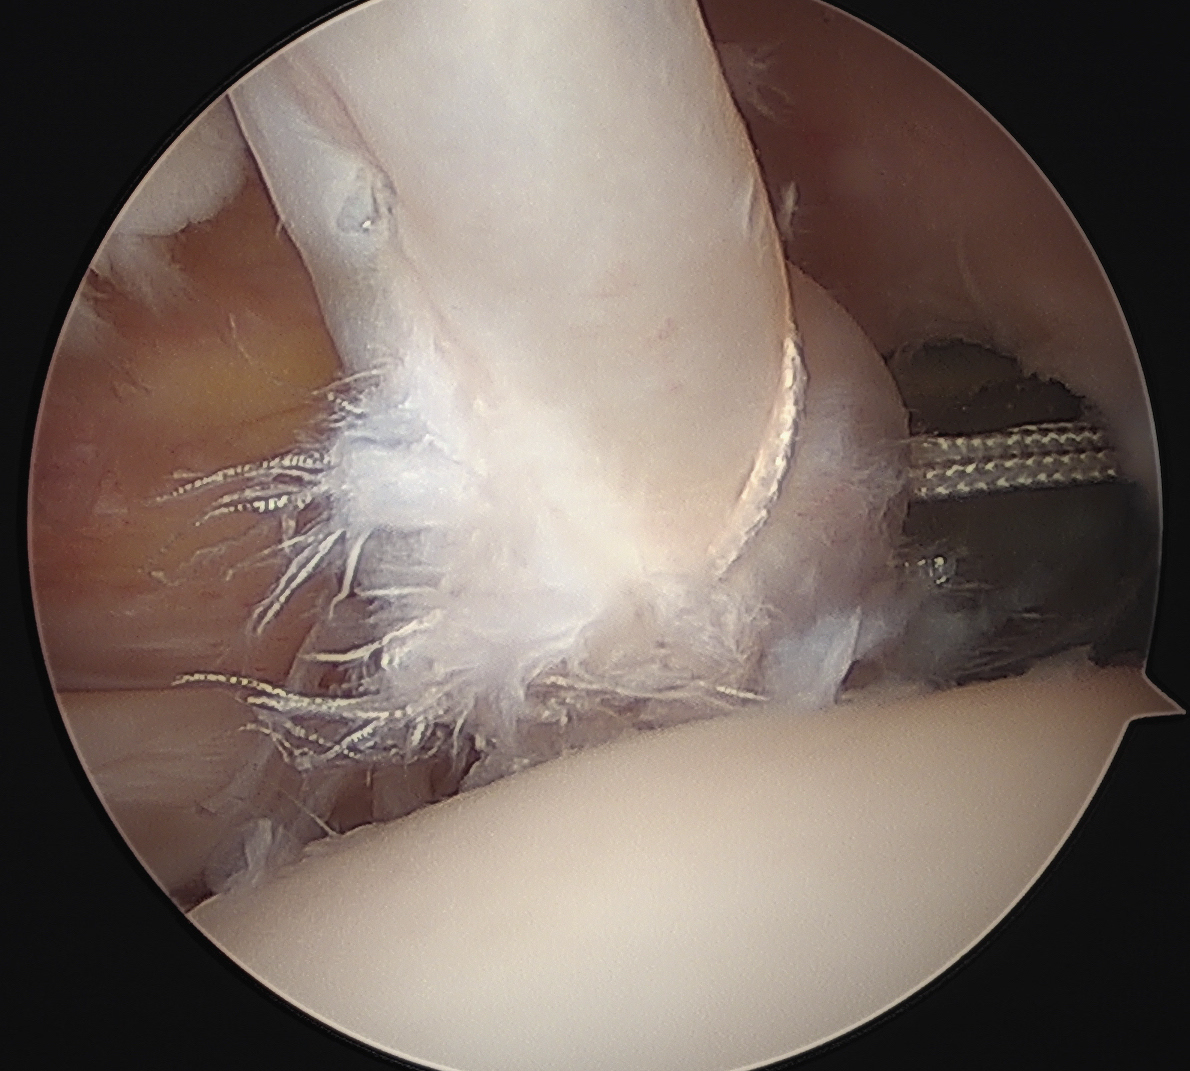

Arthroscopy

Medial subluxation of LHB

Medial subluxation of LBH with subscapularis tear